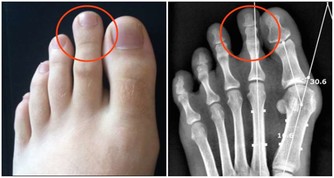

②尿無力、尿距短,或是前列腺增生、前列腺癌。

如果是增生或癌症的話,一般不會痛,只是會出現尿無力、尿距短。

此外,排尿異常有很多種,包括分叉、噴灑、尿流過細、尿距短、尿流中斷、滴尿等。這些症狀和泌尿生殖道其他疾病的表現也非常相似,所以,只要出現這些症狀,就要開始注意身體了。